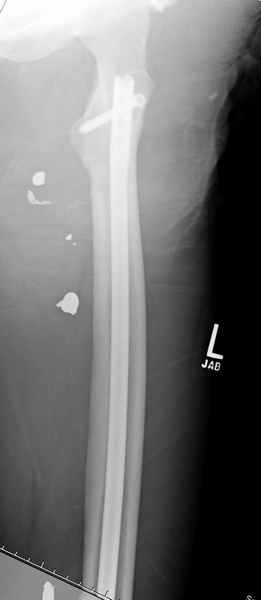

Учитывая, что больной получил травму не во время визита в церковь, и он является одним из представителем 40 миллионного “outstanding itizen”, без медицинской страховки, без работы в свои 39 лет, и без надлежающей ортопедической дисциплины у которого отсутсвует страх стрессового перелома, было рекомендовано оперативное лечение: профилактическое антеградное интрамедуллярное штифтование.

Выглядит агрессивно, и обычно госпиталь, беря финансовые расходы, остается в убытке, но мы всё же посчитали, что издержки от штифтования намного меньше, чем возможные финансовые и моральные издержки лечения таких больных, но с осложнением.

Методика штифтования при отсутствии большой зоны перелома как при онкологических профилактических штифтованиях, расверливание интрамедуллярного канала проводим с предварительным наложением дополнительного дренажного отверстия в дистальном отделе бедра (в данном случаи в канале оставили 6.5 мм канюлированный шуруп), иначе при создании давления в канале во время сверления имеется опасность эмболизации легочной артерии тромбом.